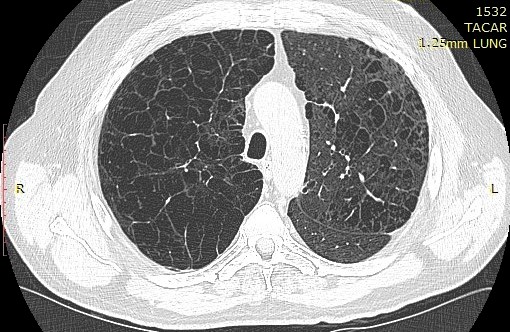

Presencia de enfisema por tomografía computada con espirometría normal

El enfisema a menudo está presente antes de que los resultados de la espirometría se vuelvan anormales, particularmente entre los hombres negros. Confiar únicamente en la espirometría para diferenciar la salud pulmonar de la enfermedad pulmonar puede resultar en un insuficiente reconocimiento del deterioro de la salud respiratoria. Annals of Internal Medicine, 19 de julio de 2022.